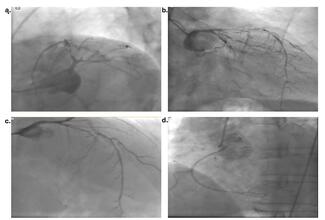

Murat Akçay, MD; Muhammed Cemallioglu, MD; Esra Temiz Lafcı, MD

The authors present an interesting and rare example of the similarity of coronary vasospasm developing after intense exercise to severe atherosclerotic stenosis to draw attention to the possible consequences of misdiagnosis.